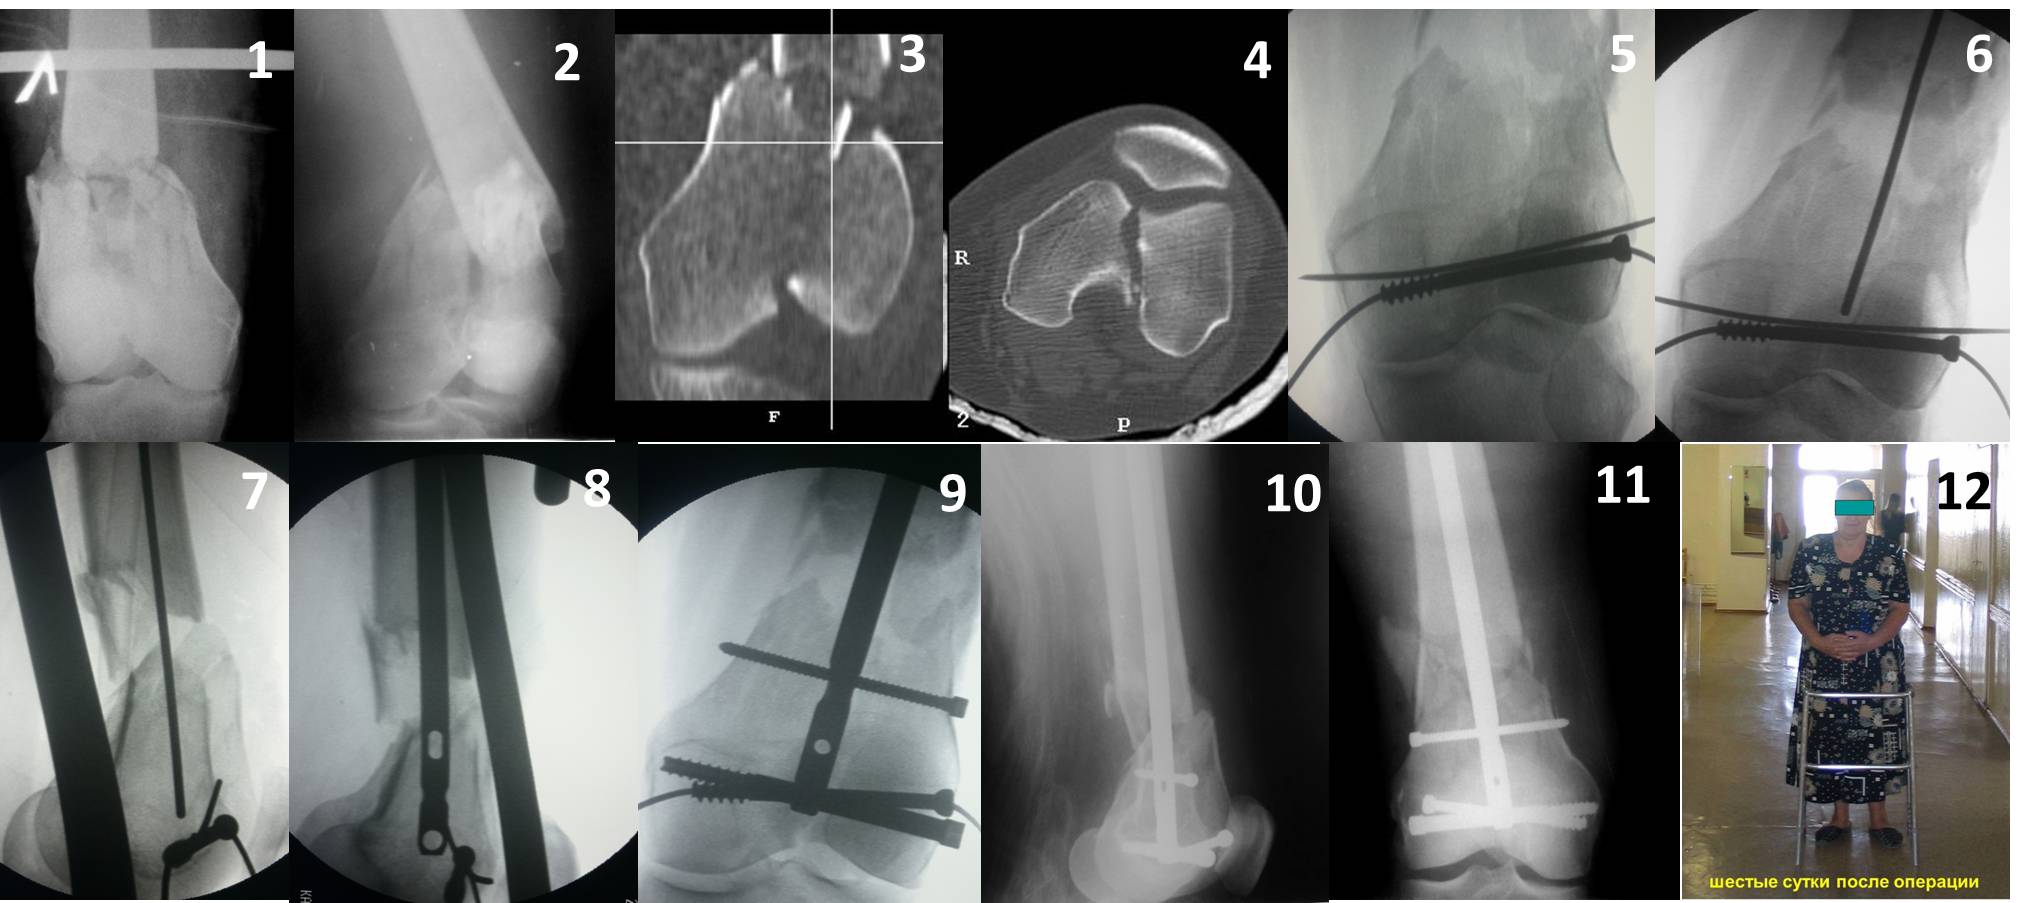

Ответ на эту часть Вашего поста – вложенный файл. Больная оперирована неделю назад по поводу открытого перелома дистального эпиметафиза бедренной кости. После операции она идёт в рентгенкабинет для выполнения послеоперационной контрольной рентгенографии, представленной на слайдах 10 и 11. Узнав, почему её фотографируют, просила передать Вам, Антон, привет.

Антеградное штифтование не очень годится при переломах типа C3, когда есть многооскольчатость именно суставной поверхности. А при переломах типа C1 и С2, т.е. и в обсуждаемом случае тоже, он как раз вполне оптимален. На межфрагментарную компрессию как-то не приходилось так драматически полагаться при интрамедуллярном остеосинтезе, результаты хорошие без нее были.

И уже лет шесть мы используем возможность ввести в дистальное овальное отверстие 3 винта, которые именно запираются в этом отверстии, не люфтят, а обеспечивают угловую стабильность - см картинку.

Получается и стабильно, и очень дистально, нижний край отверстия в 3 мм от дистального конца гвоздя.

С моей точки зрения, безусловная ценность предложенного Вами, Александр Николаевич, стержня состоит в возможности введения блокирующих винтов максимально близко к суставной поверхности дистального отломка, что значительно расширяет показания для применения интерлокинга. Можно предположить, что в техническом плане таким образом ввести блокирующие винты является непростой задачей. Кроме того, все они расположены в одной плоскости на небольшом расстоянии друг от друга.

Мне представляется, что конструкция с максимальными прочностными характеристиками будет иметь вид предложенной во вложенном файле. Такую конфигурацию расположения блокирующих отверстий на дистальном конце имеет стержень для большеберцовой кости фирмы ChM. Для бедренной кости такой стержень мне неизвестен. Поэтому в необходимых случаях (хорошо, что такие случаи встречаются не часто), как вариант, мы используем custom made стержень.

В приложении пример недавней операции, C3, открытая репозиция, фиксация мыщелков спицами и винтами, ретроградный синтез большеберцовым гвоздем 10,5 мм диаметром, винты 5 мм.